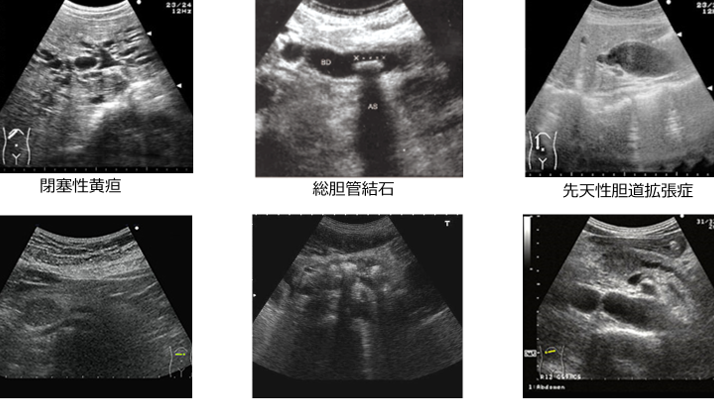

腹部エコーは、超音波を利用して内臓の状態を確認する検査です。この検査では、肝臓、胆嚢、腎臓などの内部構造や異常を非侵襲的に調べます。内臓の病変や疾患を早期発見できるため、多くの人にとって重要な健康診断の一環となります。

腹部エコーは、内臓の健康状態を評価する重要な手段です。この検査では、肝臓や胆嚢、腎臓などの状況を詳しく確認できます。以下に具体的な内容を示します。

腹部エコーは、各臓器の構造や機能を視覚化します。例えば、

- 肝臓: 肝硬変や脂肪肝の兆候が見つかることがあります。

- 胆嚢: 胆石や炎症がないかチェックできるため、異常が早期に発見されます。

- 腎臓: 腎結石や腫瘍なども確認できるため、適切な対策が可能です。

このように、それぞれの臓器について詳細な情報を提供し、健康管理に役立ちます。

疾患の早期発見

腹部エコーによって、多くの疾患が早期に発見されます。たとえば、

- 肝疾患: 進行する前に治療方針を決定できます。

- 胆道系疾患: 胆石症や胆管炎など、大きな問題になる前に対処可能です。

- 腎疾患: 腎機能低下につながる病気も早期に察知できます。